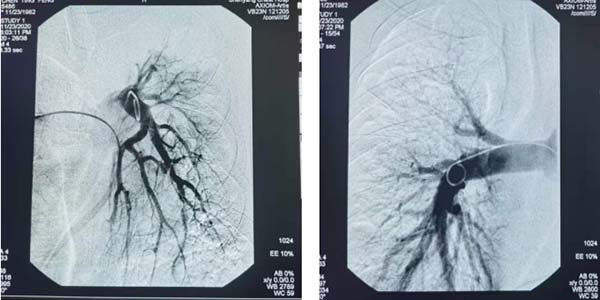

患者咯血量很,内科止血疗效不佳,随时可能因大咯血窒息危及生命。介入科张申众主任会诊后建议急诊行介入止血治疗,考虑患者肺部病灶多发,肺内部分病灶坏死形成空洞有可能合并肺动脉参与供血。经讨论决定行胸主动脉、联合肺动脉造影寻找患者出血血管。

胸主动造影造影提示右支气管动脉支气管动脉迂曲扩展与右侧肋间动脉共干,左肺支气管动脉、左侧胸廓内动脉造影剂外溢。

最后应用猪尾管于左右肺动脉主干造影,未见出血血管。

窒息是大咯血病人的最主要、最常见死亡原因,大咯血90%来自支气管动脉,故支气管动脉栓塞是最有效治疗方法。但少数患者同时合并肺动脉供血,此时还应对肺动脉进行血管造影检查,一旦明确出血血管,同时应进行相应部位肺动脉血管栓塞。这项技术的开展,突破我院咯血介入技术瓶颈,给难治性大咯血患者带来了福音。